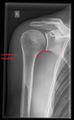

أشعة إكس

-

CR. shoulay film.

Transaxillary conventional radiography

Y-projection conventional radiography